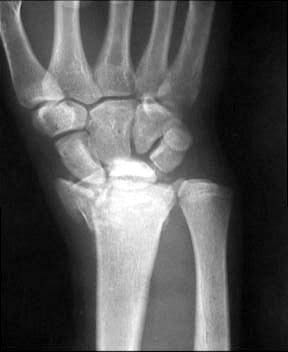

Больной из соседнего района 17 лет получил травму 8 09 03. Перелом по классификации E.Muller -В2

Неполный внутрисуставной перелом лучевой, тыльного края (Barton) Наложена гипсовая повязка рис 08 09. Через месяц на контрольной рентгенограмме найдено вывих л\з сустава. Рентгенограмма при обращении в нашу больницу 21 10 03 рис 21 10. На данные момент имеется умеренно выраженная контрактура, умеренные нейровегетативные нарушения.Обдумываем несколько вариантов лечения:1) Продолжить консервативное лечение и провести артродез, если останется болевой синдром.2) Провести открытую репозицию, устранить вывих, фиксировать отломок пластиной по тыльной поверхности.3) Провести артродез в лучезапястном суставе